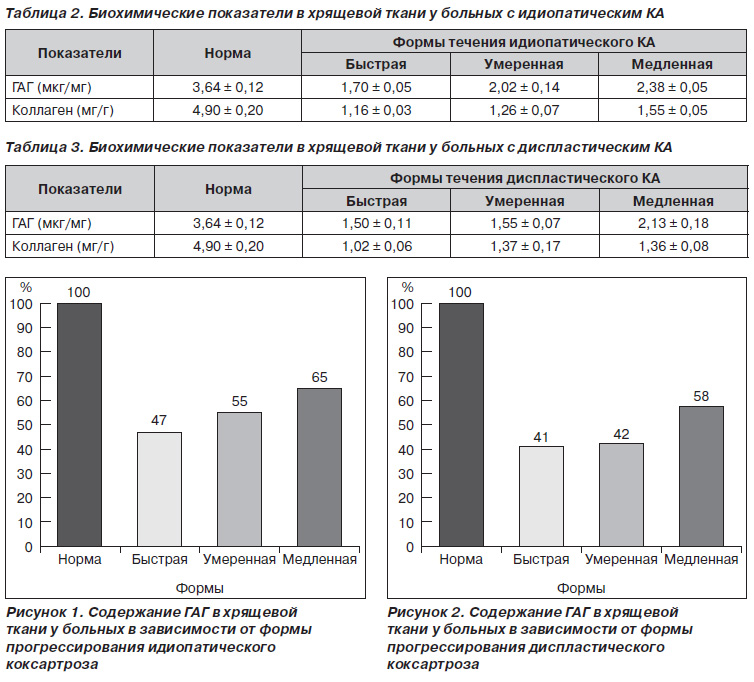

Данные, полученные при исследовании хрящевой ткани у больных с коксартрозом, свидетельствуют о снижении содержания органических компонентов соединительной ткани (табл. 2, 3, рис. 1–4).

Незначительные изменения наблюдали в содержании коллагена в хрящевой ткани больных с диспластическим коксартрозом как при умеренной, так и при медленной форме течения: 28 % относительно нормы, в абсолютных цифрах — 1,37 ± 0,17 мг/г и 1,36 ± 0,08 мг/г соответственно. Наиболее выраженное снижение коллагена в хрящевой ткани при быстрой форме течения диспластического коксартроза — 21 % от нормы, в абсолютных показателях — 1,02 ± 0,06 мг/г (табл. 3, рис. 3).

Аналогичные изменения наблюдали и в концентрации основного белка соединительной ткани — коллагена, который имеет более выраженное отклонение от нормы у больных с идиопатическим КА. Так, если в норме содержание коллагена составляет 4,90 ± 0,20 мг/г, то у больных с идиопатическим КА медленной формы течения он снижен до 1,55 ± 0,05 мг/г в абсолютных показателях, в процентном отношении — 31 % от нормы. Наиболее выраженное снижение содержания коллагена при умеренной и быстрой форме в процентном отношении составило 27 и 24 % относительно нормы, в абсолютных цифрах — 1,26 ± 0,07 мг/г (умеренная) и 1,16 ± 0,03 мг/г (быстрая) (табл. 2, рис. 4 ).

Течение заболевания определяется метаболическими изменениями в компонентах органической основы хрящевой ткани. У больных с быстрым течением КА патологические нарушения более выраженные, особенно в показателях гликозаминогликанов.

Таким образом, полученные нами данные при исследовании хрящевой ткани больных с коксартрозом дают возможность предположить, что происходит нарушение метаболических процессов, как синтеза коллагена, так и ГАГ, и эти изменения приводят к развитию заболевания на ранних этапах и углублению патологического процесса. Уровень этих нарушений определяет степень развития патологического процесса.

1. У больных как с идиопатическим, так и с диспластическим коксартрозом развитие патологического процесса происходит на фоне метаболических нарушений органической основы хрящевой ткани. Это подтверждают полученные нами данные исследования биохимических маркеров метаболизма соединительной ткани — коллагена (основного белка хрящевой ткани) и содержание гликозаминогликанов, которые определяют биомеханические и физиологические свойства хрящевой ткани.

2. Наиболее глубокие изменения биохимических показателей (коллагена, гликозаминогликанов) суставной хрящевой ткани наблюдались при быстрой форме прогрессирования идиопатического и диспластического коксартроза.